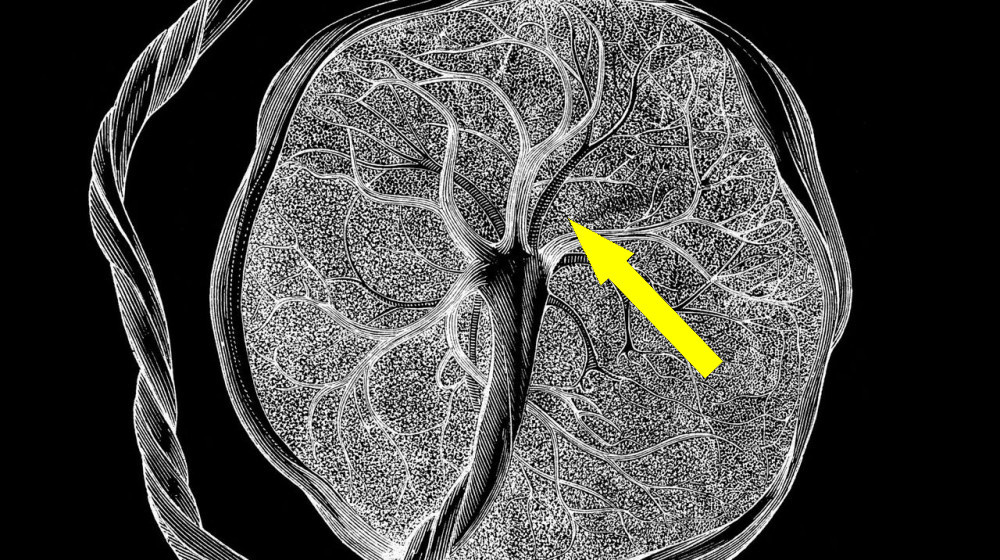

Обнаруженные клетки получили название «тимостромальные клетки беременности» (ТКБ), поскольку они проявляются исключительно во время вынашивания плода и исчезают по окончании этого процесса. Эти клетки отличаются от ранее известных типов клеток человека, таких как стволовые или иммунные клетки. Их уникальность заключается в том, что они обладают способностью к мультипотентности – то есть могут превращаться в разные типы тканей, что делает их крайне интересными для биомедицинских исследований.

Истоки этих клеток ученые связывают с иммунной системой матери и плацентой. В ходе многоступенчатых исследований было выявлено, что ТКБ образуются из определенных клеток в стенке матки и в дальнейшем активно участвуют в формировании тканей плода, а также в регенерации организма матери. Заметим, что ранее считалось, что такой тип клеток характерен только для определенных тканей, например, костей или костного мозга, а тут – появились новые, уникальные, ранее не описанные виды.